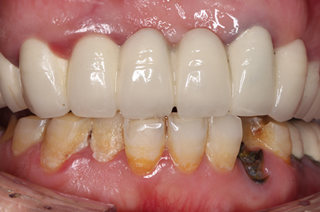

种植成功后的牙齿

经过麦芽口腔医师团队的努力,饱受牙齿缺失困扰的香港美女面点师郄女士,终于摆脱长期无法品尝美食的痛苦,露出了久违的笑容。郄女士表示:“手术全程就是在打麻药的时候有点痛,就像蚊子咬一样,是在可以接受的范围,手术过程整个工作人员都很贴心,每一步都告诉我接下来要做什么,我觉得把牙齿问题交给麦芽,交给麦芽种植医师团队我很放心”。